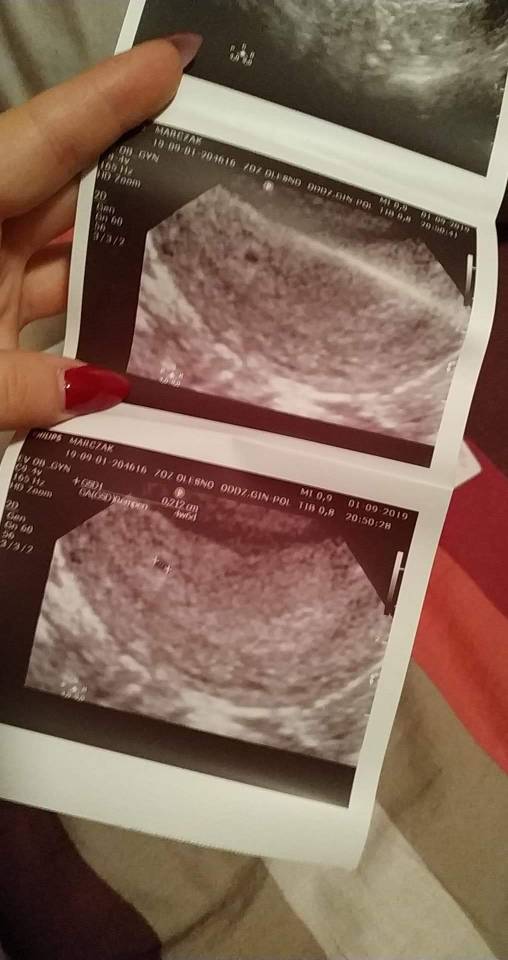

Dostałam duphaston 2 razy dziennie i pierwsze zdjęcie mojego kropka [emoji3590]Zobacz załącznik 1017234